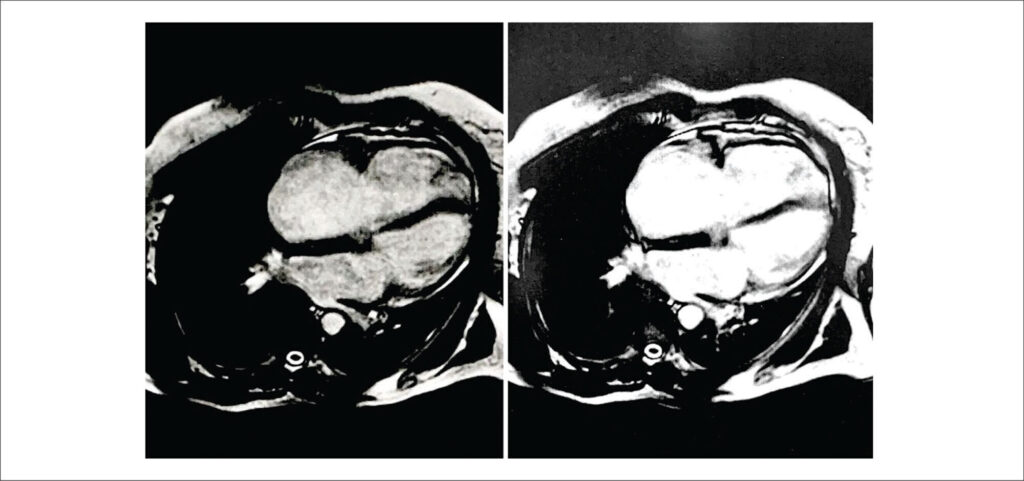

Anomalia de Uhl: Relato de Caso e Diagnóstico Diferencial em Adulto

A anomalia de Uhl (AU) é um distúrbio exclusivo do ventrículo direito (VD) que se caracteriza pela ausência do miocárdio total ou parcial, de forma que a parede ventricular fica composta pela superposição de endocárdio e epicárdio, sem qualquer tecido gorduroso, processo inflamatório ou infiltrativo. A musculatura dos átrios, o septo interventricular e o ventrículo esquerdo (VE) não estão envolvidos no processo.,

As manifestações clínicas são decorrentes da insuficiência ventricular direita (IVD). Formas com acometimento parcial podem ser pouco sintomáticas e permanecer por longos períodos sem diagnóstico, podendo ser confundidas com outras patologias mais frequentes que acometem o coração direito na vida adulta.,